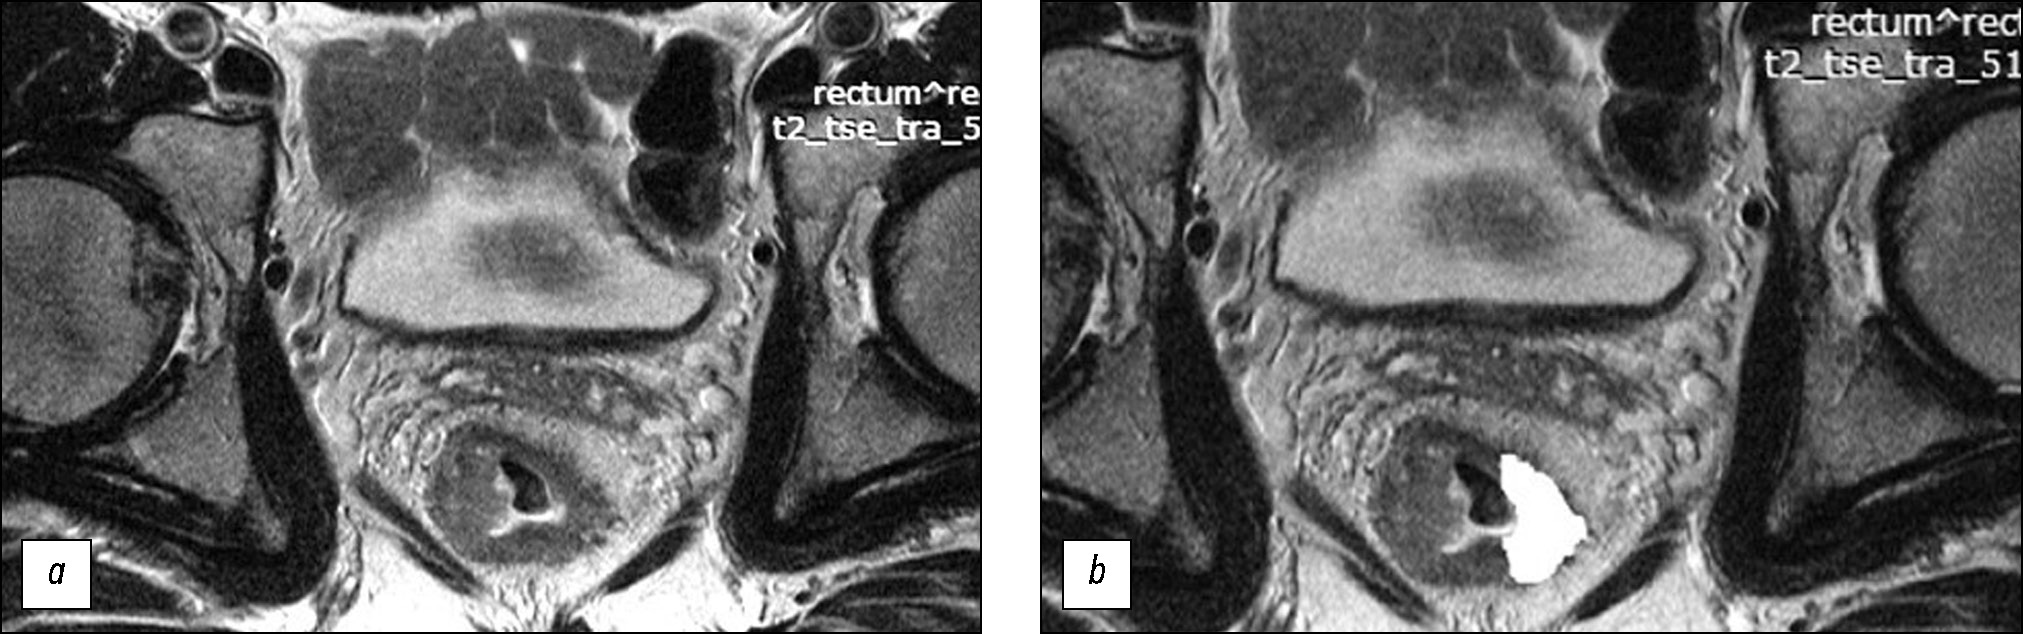

Prediction of the efficacy of neoadjuvant chemoradiotherapy in patients with rectal cancer based on a texture analysis of T2-weighted magnetic resonance tumor image obtained at primary staging

AIM: To assess the texture characteristics of locally advanced rectal cancer in primary T2-weighted imaging (T2-WI) as a potential predictor for the efficacy of standard neoadjuvant chemoradiotherapy and develop a prediction system for the efficacy of neoadjuvant chemoradiotherapy based on them.

MATERIALS AND METHODS: The retrospective study enrolled 82 patients with locally advanced rectal cancer who received combination treatment with neoadjuvant chemoradiotherapy. Patient data were divided into the training (n=58) and control (n=24) sets. For texture analysis, primary high-resolution T2-WI at the level of the tumor center, oriented perpendicular to the intestinal wall, was used. The texture analysis was performed by second-order statistics based on the gray-level co-occurrence matrices using MAZDA ver. 4.6 featuring the calculation of 11 texture parameters. In the training set, based on the morphological assessment of surgical specimens, significantly different texture analysis parameters were found for two groups of patients: neoadjuvant chemoradiotherapy responders (good prognosis group) and nonresponders (poor prognosis group). Accordingly, a scoring system was created for assessing the efficacy of neoadjuvant chemoradiotherapy. The system was tested on the control set, and diagnostic efficacy parameters were determined.

RESULTS: In the training set, the good and poor prognosis groups differed significantly in five texture parameters: AngScMom (p=0.021), SumofSqs (p=0.003), SumEntrp (p=0.003), Entropy (p=0.038), and SumVarnc (p=0.015), for which the cutoff points were found. These parameters were applied to create the scoring system (excluding the Entropy parameter, which had a strong direct correlation with SumEntrp and the lowest area under the curve, and SumofSqs, which had low reproducibility). The diagnostic efficiency of the scoring system for predicting the response had sensitivity, specificity, positive-predictive value, and negative- predictive value of 72%, 69%, 70%, and 71% for the training set and 80%, 64%, 62%, and 82% for the control set, respectively. The areas under the ROC curve were 0.77 and 0.72 for the training and control sets, respectively.

CONCLUSIONS: Texture analysis of the primary T2-WI of tumors in patients with locally advanced rectal cancer allows for predicting the efficacy of neoadjuvant chemoradiotherapy with moderate diagnostic efficiency. The results suggest good prospects for further research in this area.